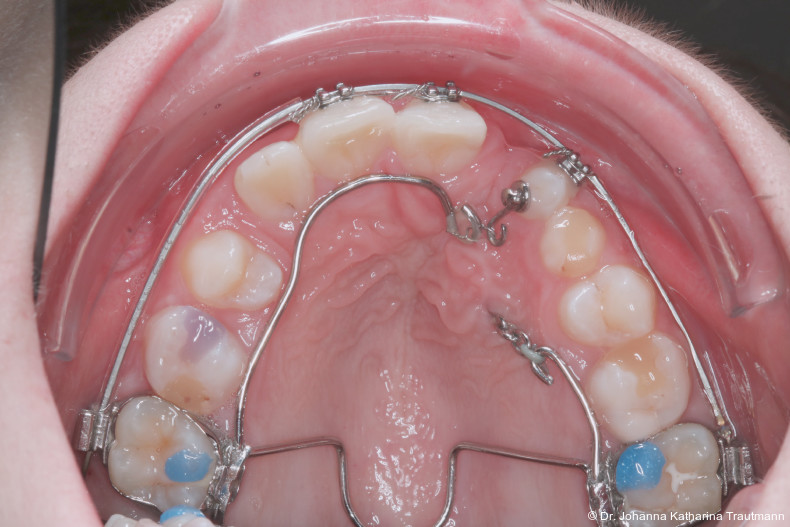

Nach transversaler Nachentwicklung der Maxilla mittels GNE nach Veltri wurde der Zahn 23 geschlossen freigelegt und an einem individualisier ten TPA nach distal angebunden. Zur Aufrichtung der Front und Mesialisierung des hypoplastischen Zahnes 22 kam zusätzlich eine 2x3Mechanik zum Einsatz. Eine rein translatorische Bewegung eines Zahnes ist auch mit einer festsitzenden Apparatur schwer zu erreichen, da der Kraftansatzpunkt nicht identisch mit dem Widerstandszentrum des Zahnes ist.7 Diese Problematik kann einerseits durch das Einbringen eines Versetzungsmomentes adressiert werden, andererseits durch eine Verlagerung des Kraftansatzpunktes. Angelehnt an den von Hong et al. beschriebenen Power Arm 8 wurde hierfür palatinal an Zahn 22 ein cranial gerichteter Hook angebracht (Abb. 3). Da Zahn 22 aufgrund seiner Hypoplasie eine verkürzte Wurzel aufwies, konnte so die Distanz zwischen Widerstandszentrum und Kraftangriffspunkt effizient reduziert werden. Eine weitere biomechanische Schwierigkeit stellte das geringe Alveolarknochenangebot im Spalt bereich mesial von 22 dar. In Bereichen mit Knochendefizit verschiebt sich das Widerstandszentrum nach apikal und wie in diesem Fall zusätzlich nach distal.9, 10 Um dem erhöhten Risiko für Kipp bewegungen entgegenzuwirken, muss hier besonders auf die Steuerung des M/F-Quotienten geachtet werden. Der vestibulär durchgebrochene Zahn 13 benötigte keine Freilegung. Um seine korrekte Einstellung zu ermöglichen, wurde die Mesialwanderung des Zahnes 16 mithilfe des TPAs korrigiert sowie eine Mittellinienkorrektur nach links mittels 2x3 Mechanik durchgeführt.